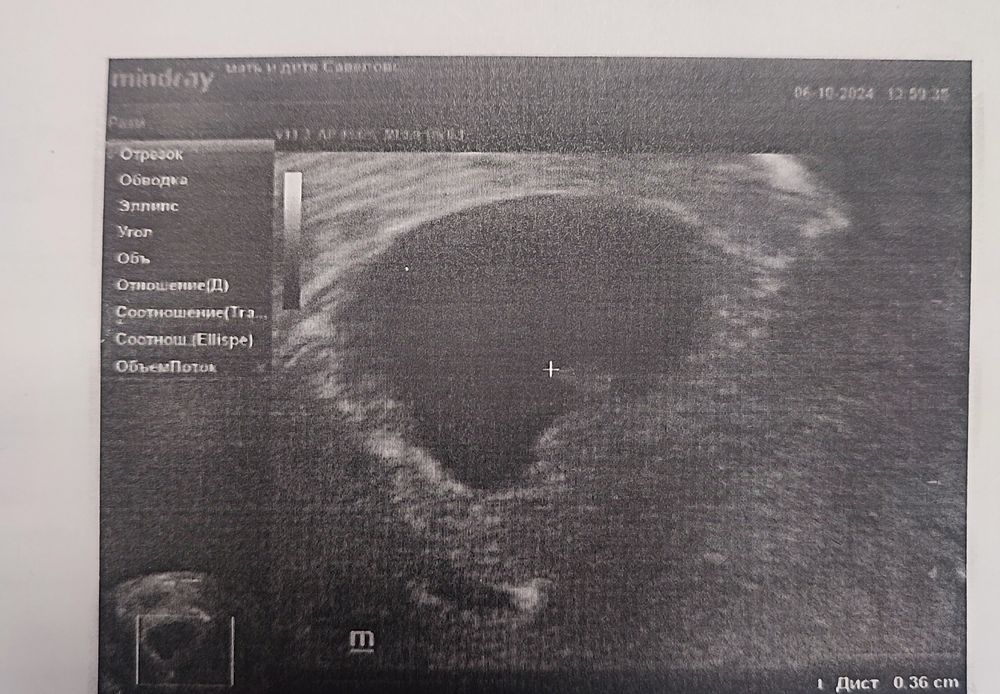

Но в целом: СВД ПЯ 17 ММ (оно уже не такое вытянутое, хоть и не ровно-круглое. Но врач сказала, что все хорошо, а я ей доверяю)

Желточный мешочек 4,6 (и тут я напряглась, как-то он слишком стремительно растет. Но поскольку я понимаю, что измерения в миллиметрах - дело такое, решила не нервничать).

Ктр 3,6, сердцебиение 99 (сначала показали цветом, потом включили. Сначала нашли какие-то единичные звуки, я снова напряглась. Но после что-то поправили, поймали ритмичное). Доктор сказала, что для такого размера ктр с ЧСС все хорошо, прийти через 10-14 дней.

Фотографию не дали, но сделали копию фото))